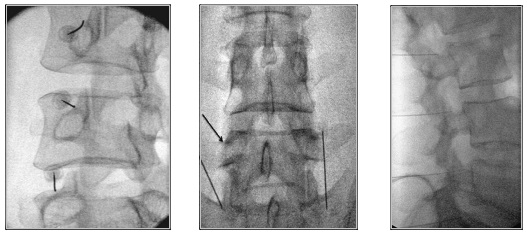

Πώς εκτελείται η διαδικασία νευρικού αποκλεισμού της άρθρωσης

Η διαδικασία μπορεί να διενεργηθεί στις αρθρώσεις του αυχένα, της ράχης και της μέσης. Με τον ασθενή σε πρηνή θέση και υπό τοπική αναισθησία εισάγεται μια βελόνα που υπό συνεχή ακτινοσκοπική καθοδήγηση φθάνει στους νευρικούς κλάδους της κάθε άρθρωσης. Μια μικρή ποσότητα αναισθητικού διαλύματος εγχέεται και αφαιρείται η βελόνα. Ο ασθενής αναπαύεται για 30 λεπτά και σε μία ώρα μπορεί να εξέλθει, μετά την αξιολόγησή του από τον θεράποντα ιατρό. Οι κίνδυνοι από τη διαδικασία είναι σπάνιοι.

Τι συμβαίνει κατά τη διάρκεια της νευρόλυσης

Χορηγείται τοπική αναισθησία για να μουδιάσει το δέρμα. Ο ιατρός κάτω από ακτινοσκοπική καθοδήγηση, εισάγει μια λεπτή ειδική βελόνα που στοχεύει το σημείο διέλευσης του μέσου νευρικού κλάδου, το οποίο βρίσκεται στη συμβολή της άνω αρθρικής και της εγκάρσιας απόφυσης του σπονδύλου στην οσφυϊκή μοίρα.

Στην πορεία ακολουθεί κινητικός και αισθητικός ερεθισμός του νεύρου. Αυτό μπορεί να οδηγήσει σε μικρούς τοπικούς μυϊκούς σπασμούς και να προκαλέσει λίγο πόνο. Μόλις ελεγχθεί η σωστή τοποθέτηση της βελόνας, χορηγείται τοπικό αναισθητικό και ακολουθεί η θερμοκαυτηρίαση του νεύρου.